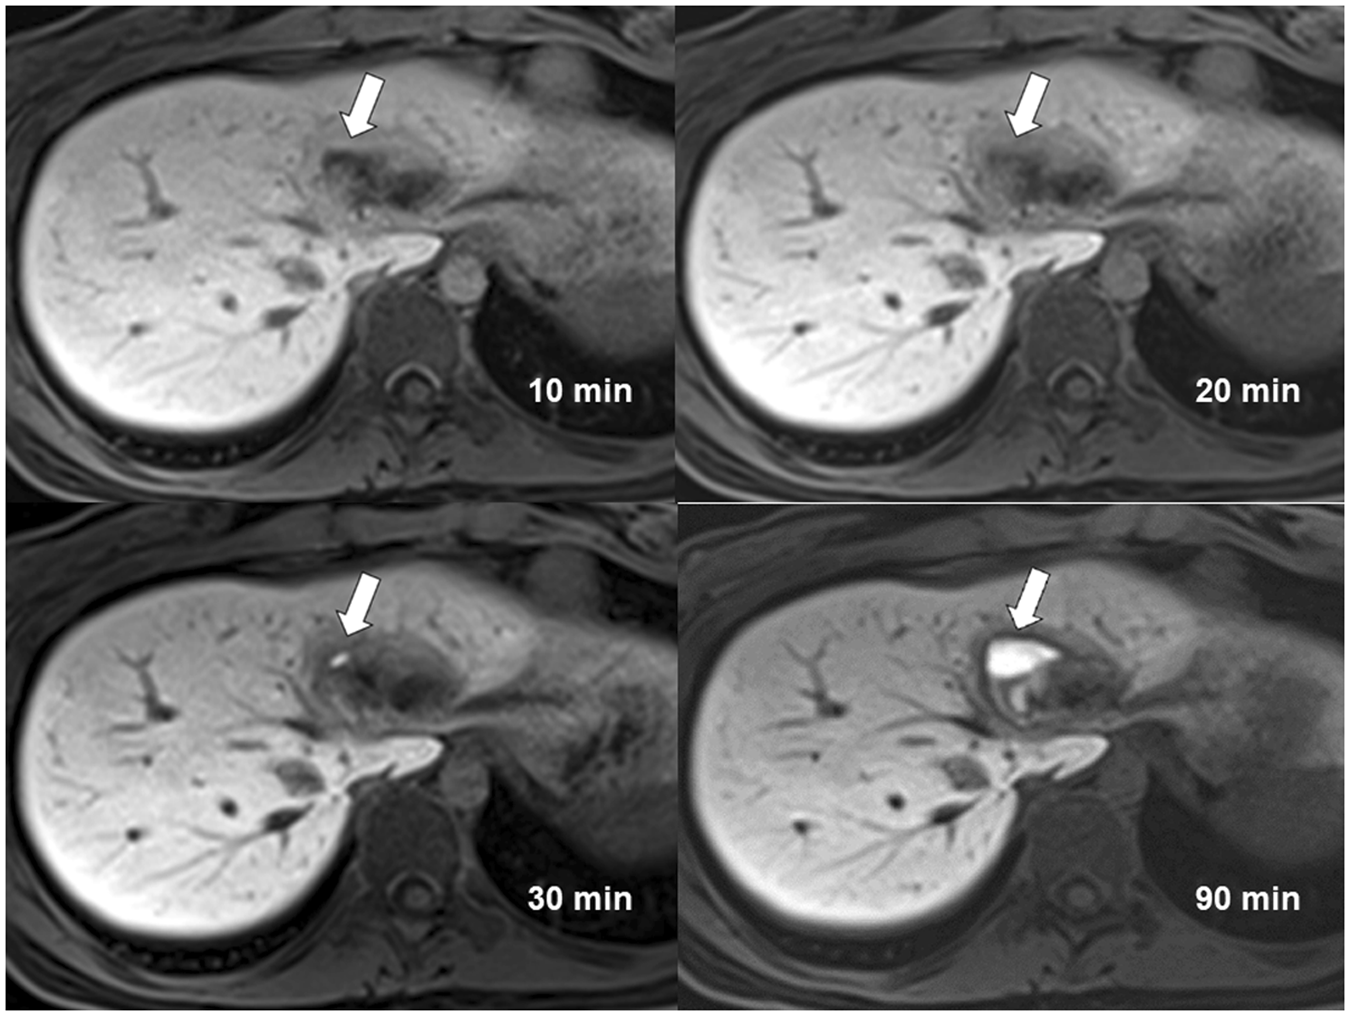

Figure 2

Contrast enhanced MR cholangiography of a 20-year-old woman with a liver injury acquired at 10 minutes, 20 minutes, 30 minutes and 90 minutes. Type I bile leak confined within liver parenchyma is most obviously detected at 90 minutes acquisition (arrow). The average scores given by three readers are 1.33 (10 minutes), 2.00 (20 minutes), 2.00 (30 minutes), 5.00 (90 minutes).